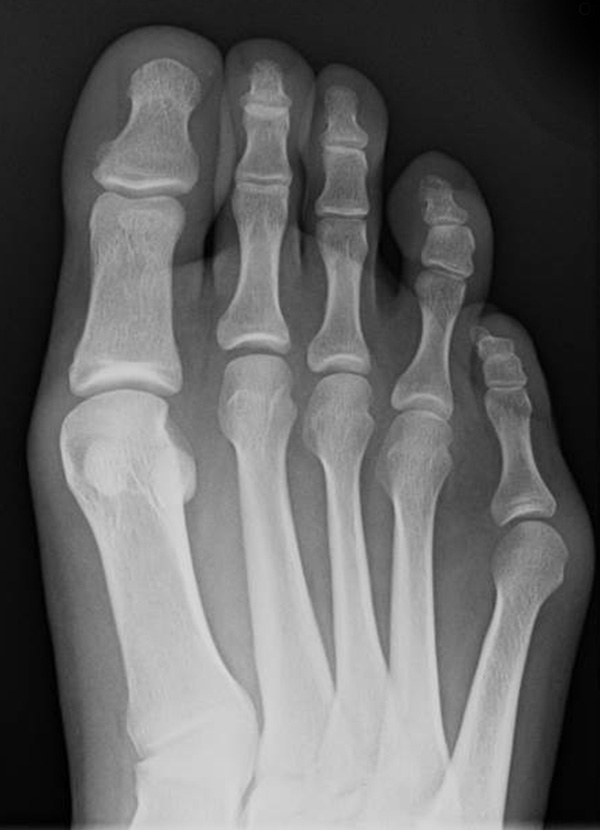

Abb. 7 a, b: Typ II Deformität mit prä- (a) und postoperativem Röntgenbild (b) mit K-Draht Osteosynthese und gleichzeitiger Hallux valgus Korrektur.